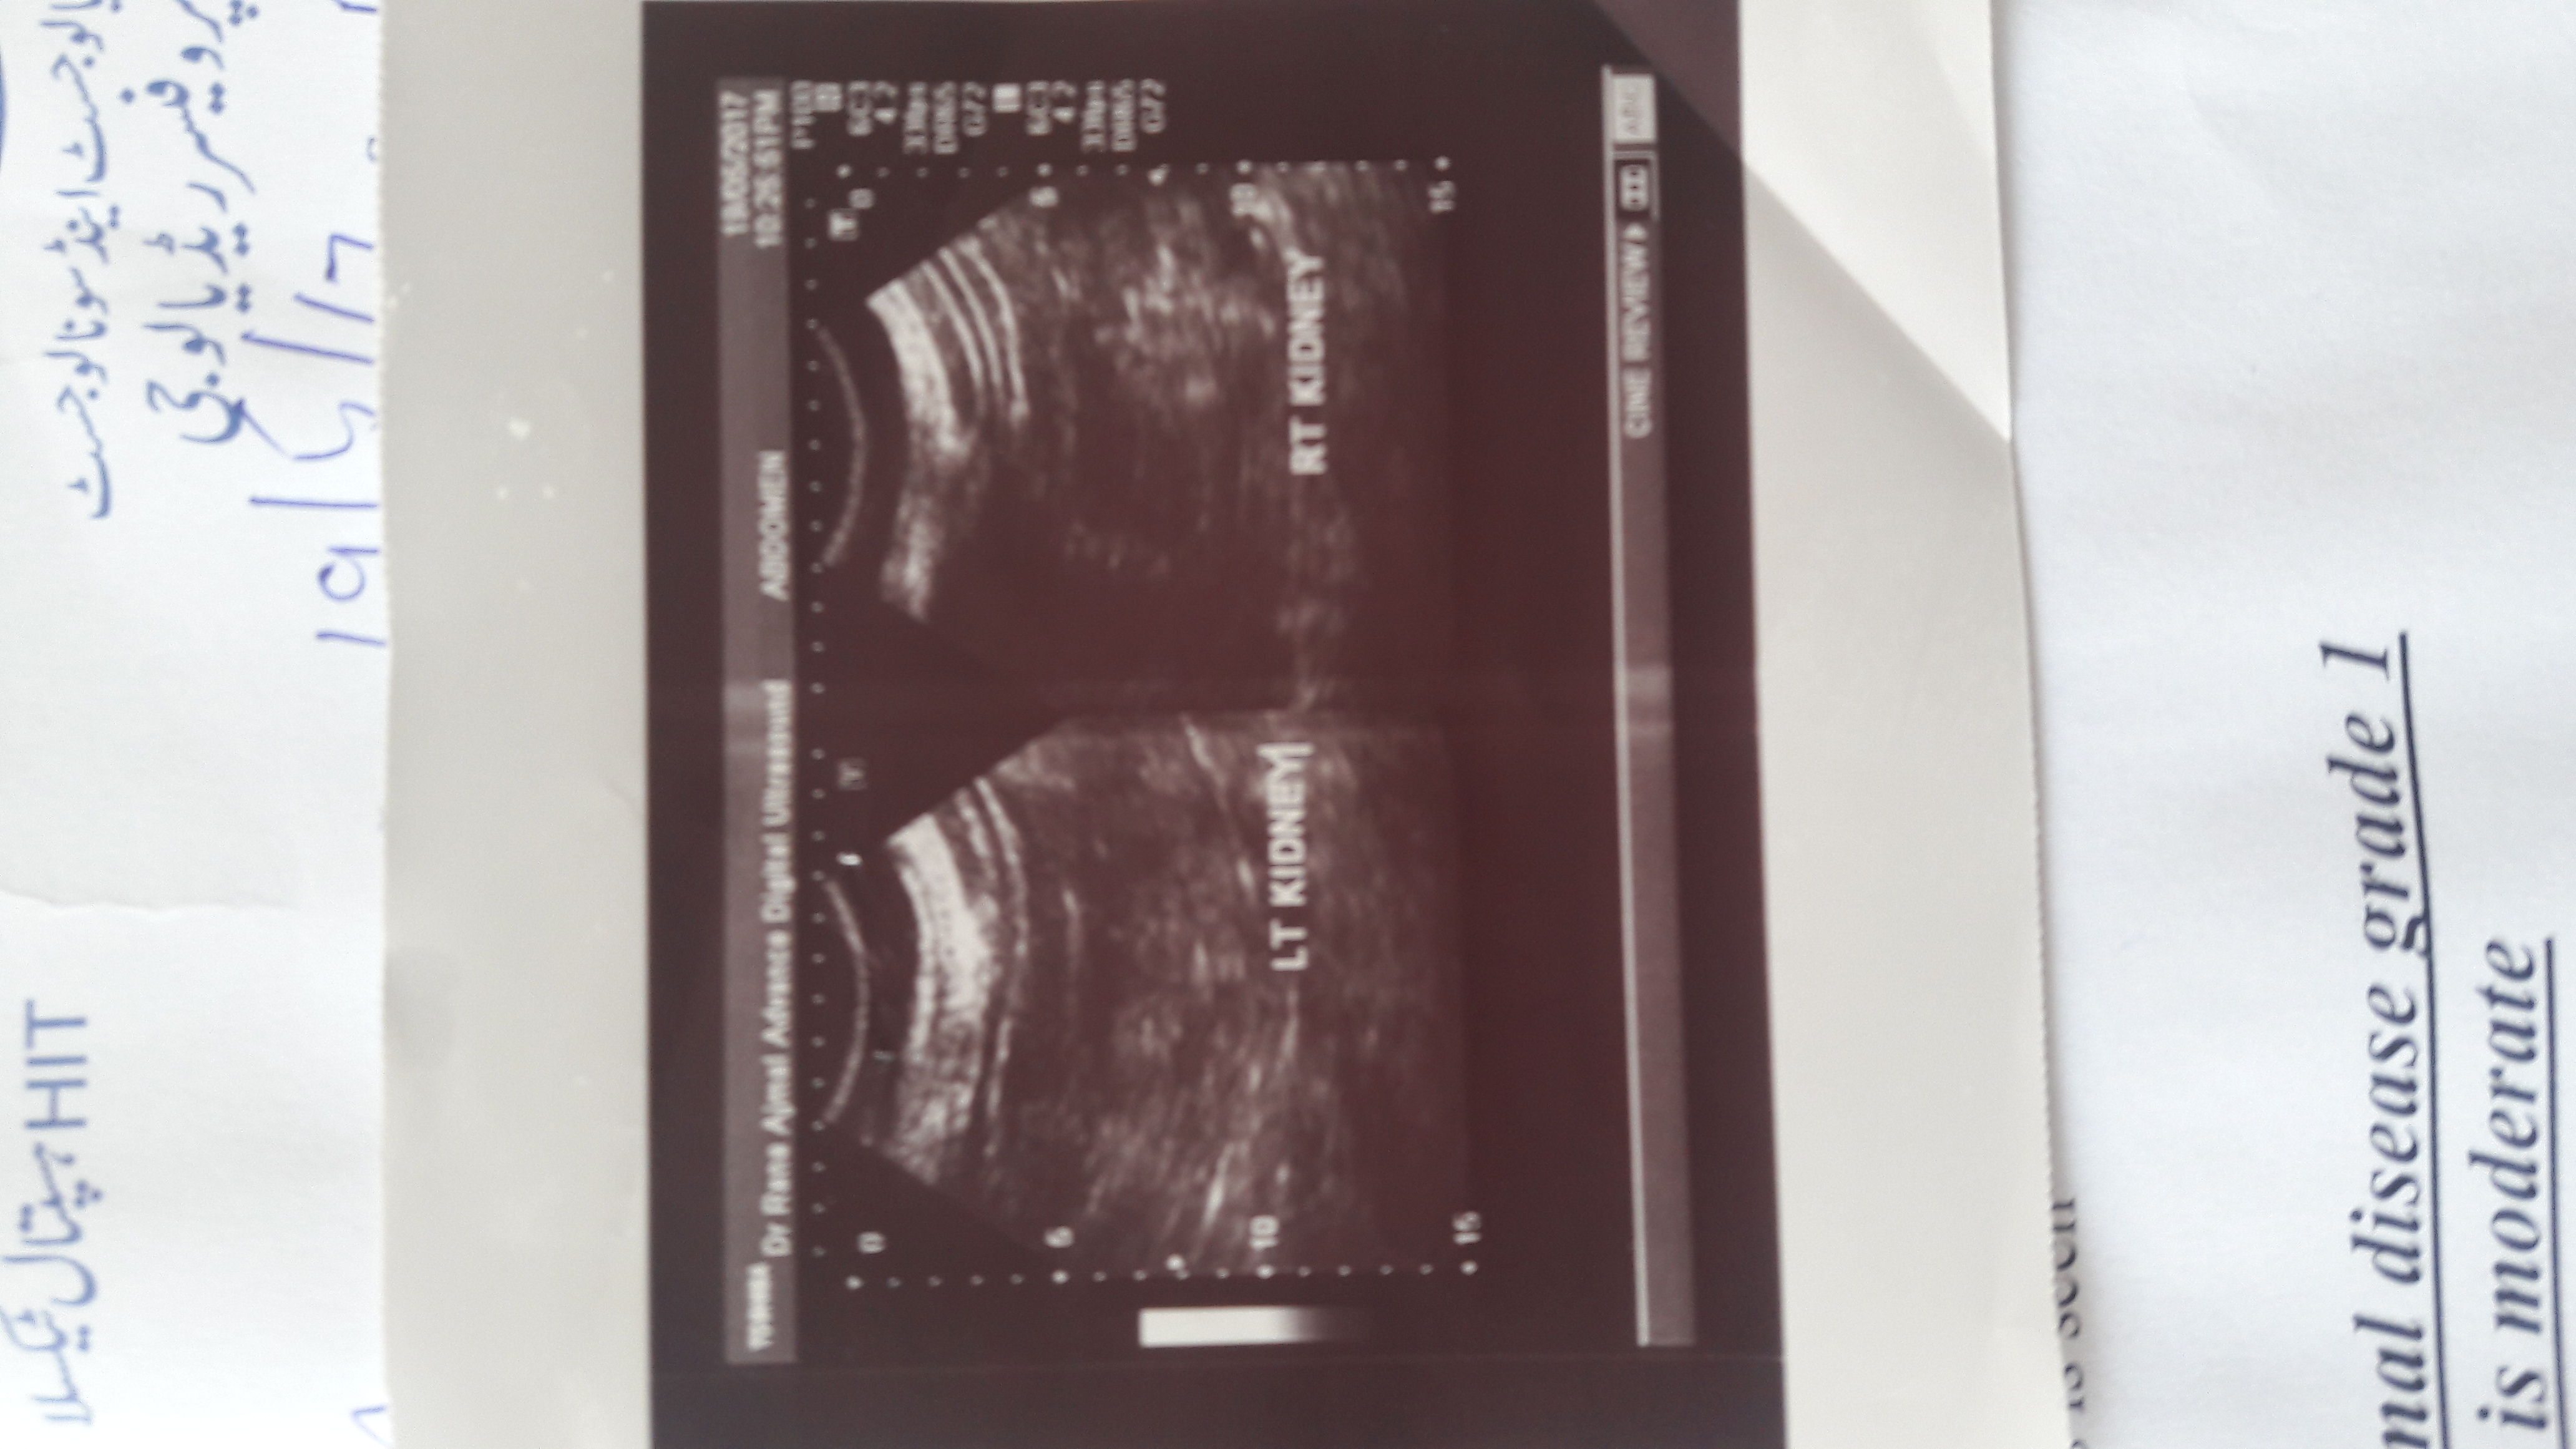

Attach Photo here: